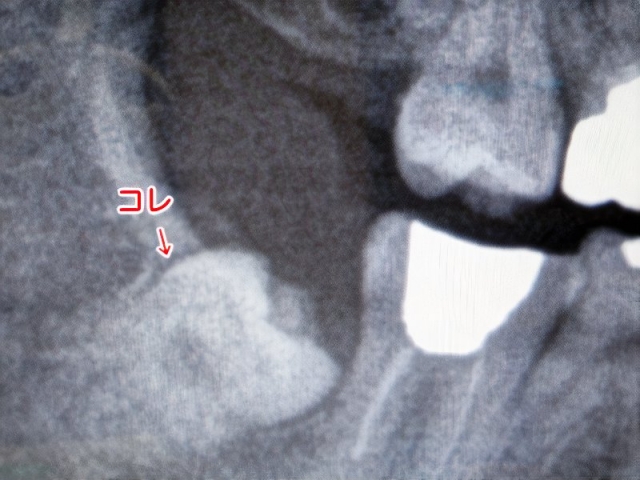

まず、僕の親不知の状態を確かめるためレントゲンを撮る事になった。僕を悩まし続けた親不知がどんな形をしているのか。親不知の歯医者さんでその全貌が明らかになるのだ。

0023_photos_v2_x2.jpg

僕の親不知

レントゲンの結果、意外な事が分かった。右下の親不知が痛んでいたのは、その上の親不知が原因だったのだ。上の親不知が下の親不知に当たって痛かったのである。上の親不知を抜けば今までの様な痛みは消えるという。